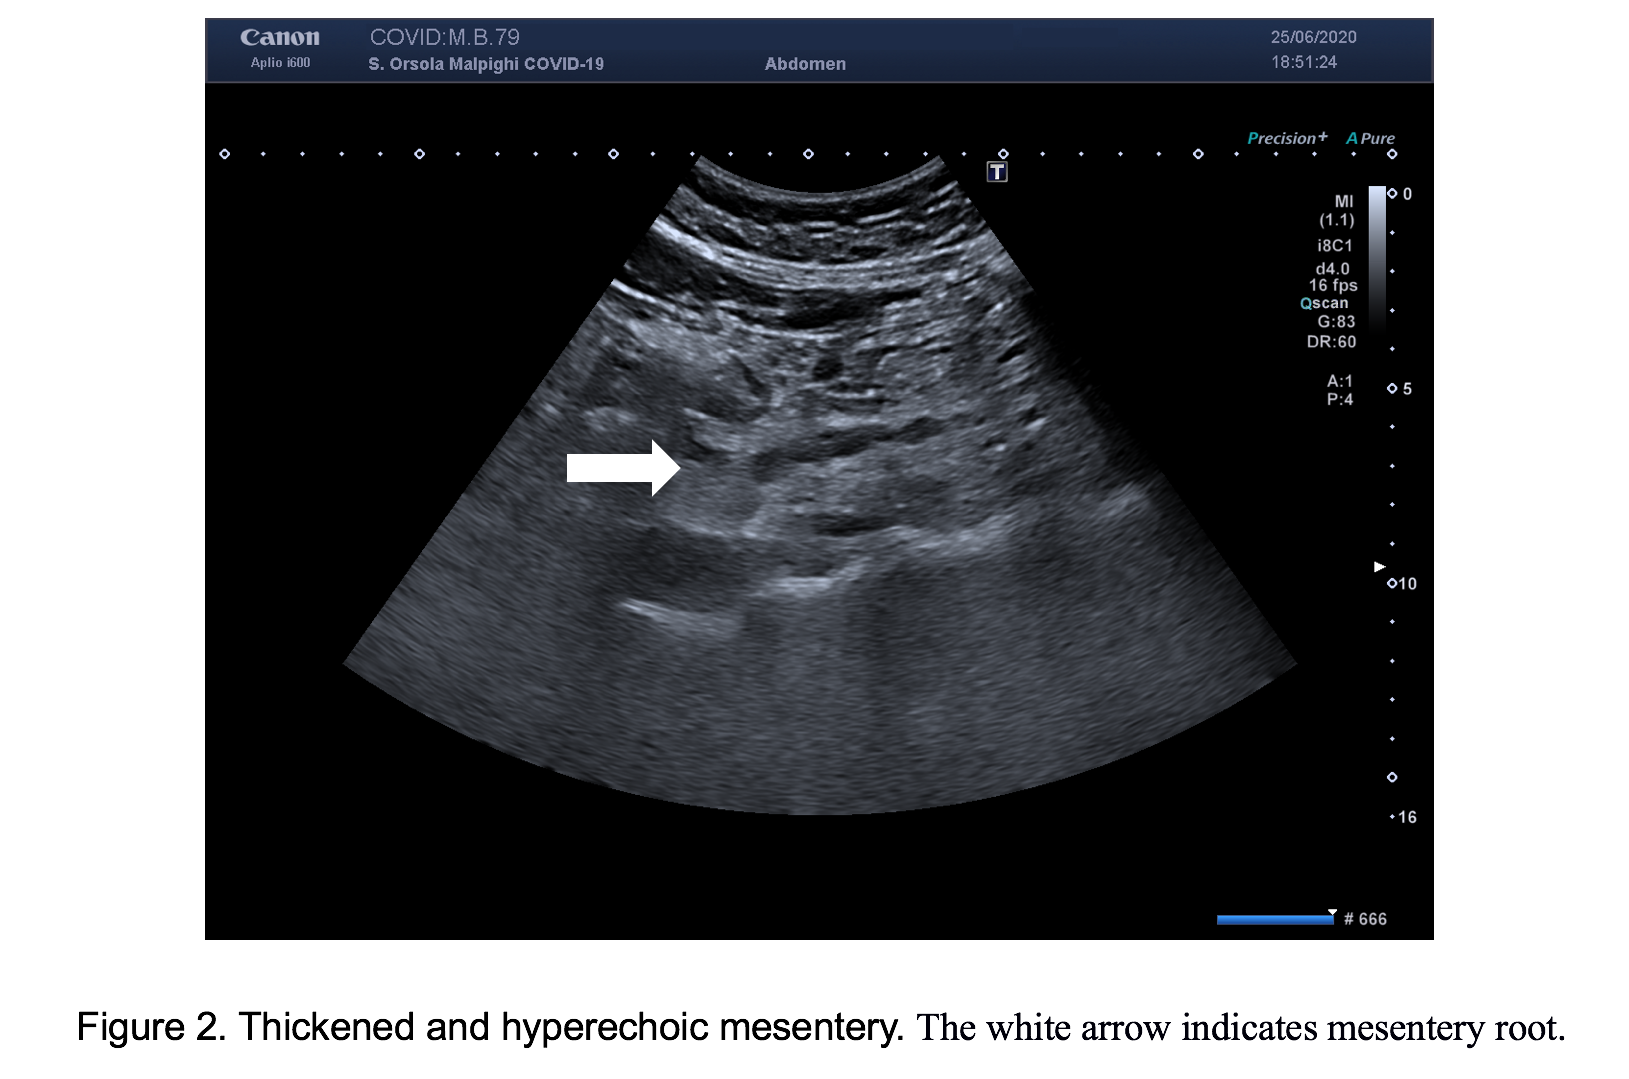

For persistent abdominal pain, we performed bowel ultrasound that showed, in both patients, dilated fluid-filled bowel loops with mildly thickened wall (3-4 mm), in different quadrants of the abdomen (Figure 1). Moreover, the mesenteric root appeared thickened and hyperechoic, with hypo-echogenicity of the adjacent retroperitoneal and meso-colonic fat, with a typical “mass effect” , suggestive of a mesenteritis. The bowel loops and the mesentery root however, did not show increased vascular flow with Colour Doppler and there was no free fluid in the abdomen (Figures 2 & 3; Video 1).

In these two patients, bowel ultrasound showed findings similar to patients with a mesenteritis, suggesting that COVID-19 could also cause inflammation to mesentery with consequent abdominal pain. Further research of patients with COVID-19 and GI symptoms are suggested to confirm these observations and to evaluate the clinical impact of bowel US in this setting.